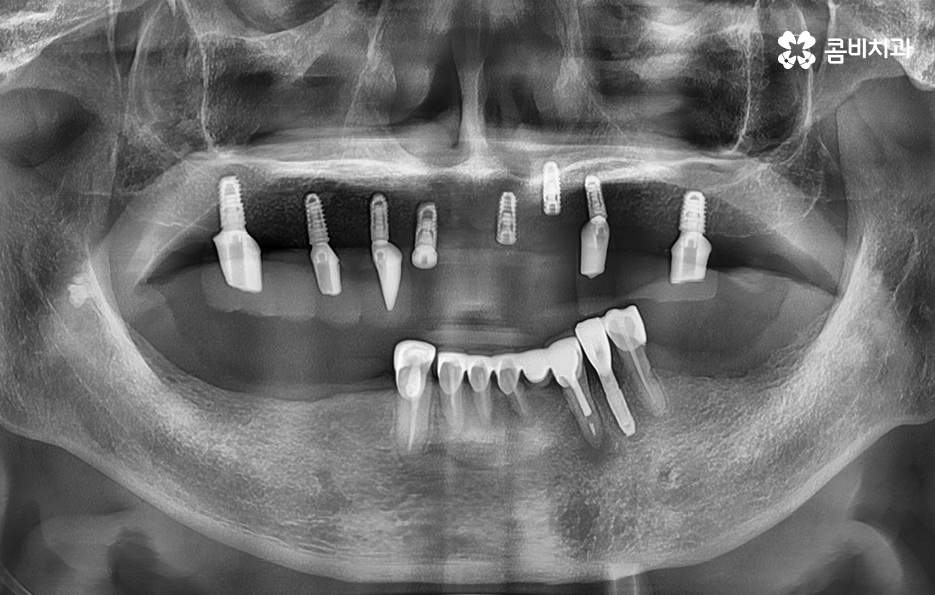

반면에 5,60대 이후에는 치주질환으로 인해 치아를 잃게 되는 경우가 많고 잇몸이 약해진 상태이거나 전신질환 등을 함께 고려해야 하는 복합적인 치료 계획을 세워야 하는 경우가 좀더 많이 있는데요

실제 치료 사례를 살펴보더라도 젊은 환자분들의 경우 원데이임플란트로도 치료가 가능한 사례가 많다면 노인분들의 경우 잇몸이 약해진 상태에서 치주염으로 치아를 잃게 된 경우가 많다보니 뼈이식을 추가적으로 받아야 하는 경우가 많이 있어요

5,60대 이후 환자 분들의 경우에는 잇몸 상태가 이미 좋지 않은 분들이 많고 전신질환이 있는 분들도 많기 때문에 임플란트 나이에 있어서는 보다 섬세한 치료가 필요한 경우가 좀더 많다고 볼 수 있어요

정리하면 임플란트 나이 단순히 나이만으로 치료 계획에 대해 쉽게 판단하기는 어렵겠지만 통계적으로 볼 때 치아의 주된 상실 원인과 임플란트의 원리에서 잇몸 뼈의 중요성을 따져볼 때는 젊은 환자분들에 비해 60대 이후 환자분들이라면 뼈이식을 추가로 받아야 한다거나 회복력과 전신질환에 대해서도 충분히 좀더 감안하여 치료 계획을 디테일하게 세울 필요가 있다는 것을 알 수 있는데요